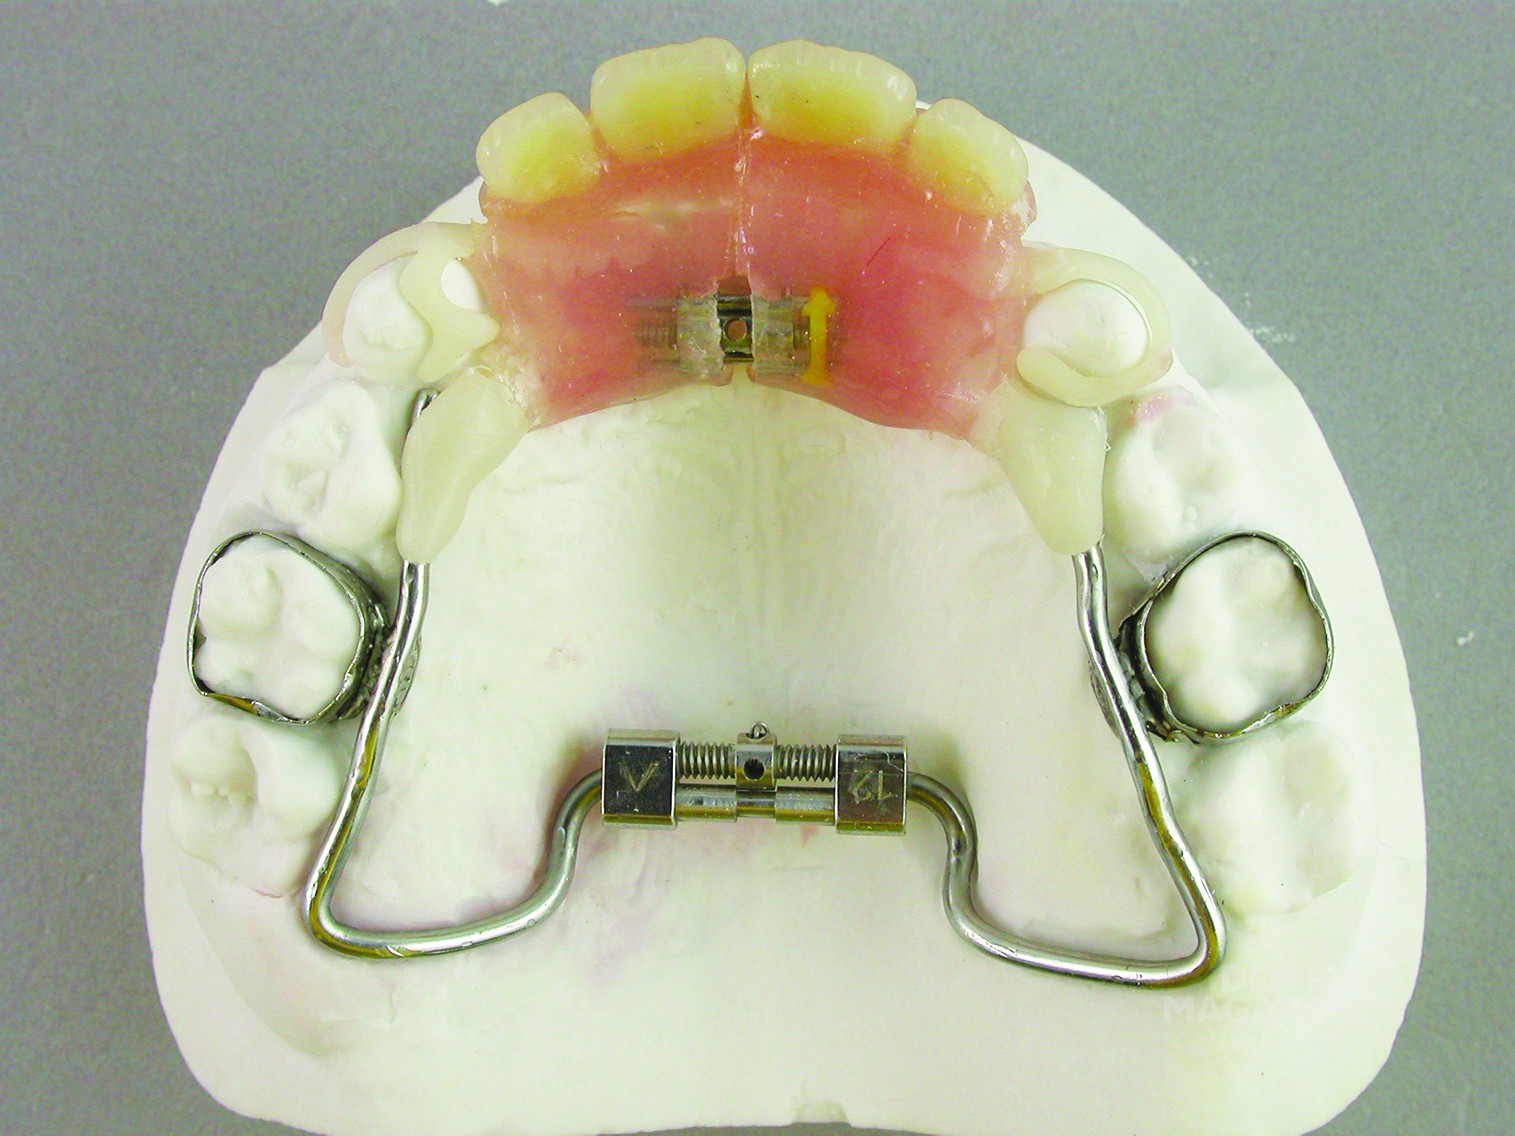

Съемные профилактические протезы: примеры и фотографии